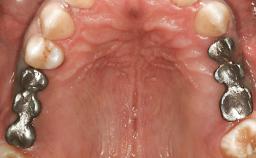

German Gallucci

Boston, United States